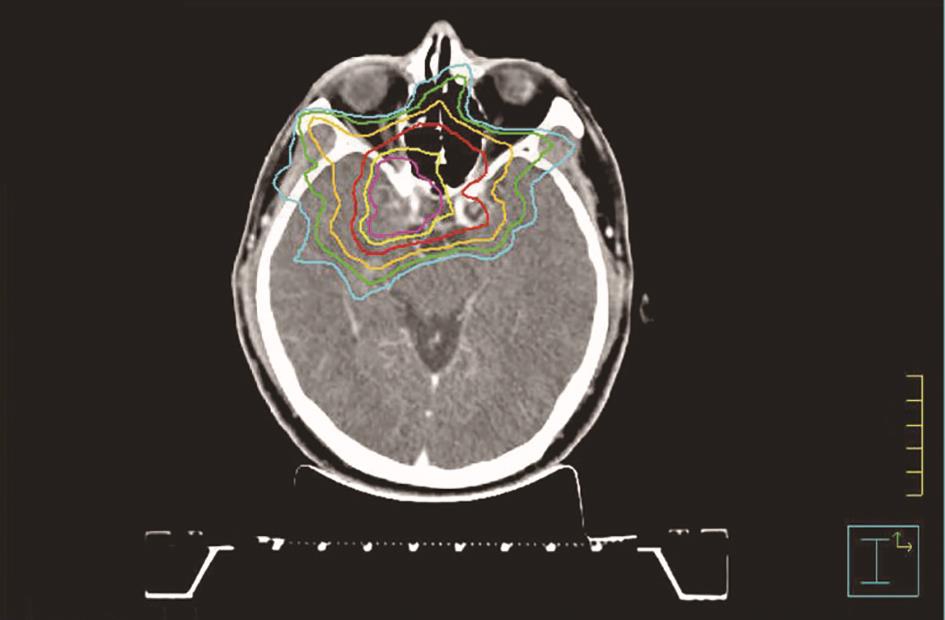

临床评价一般通过剂量分布(图1-20)和DVH(图1-21)进行评价。传统的2D计划系统中,剂量显示和计划评估非常简单。归一后的等剂量曲线叠加在治疗部位的轮廓图上。因为射野方向、形状和大小都在模拟机上事先确定,计划系统只作为剂量计算器和剂量分布显示器。此时对计划的评估只是明确规定的等剂量线是否包括靶区和剂量分布是否均匀,或借助楔形板和调整射野剂量比,使靶区得到均匀的剂量分布,并尽量避开邻近重要器官和组织。这种评估只在少数几个平面内进行。

20世纪70年代初CT的出现可以为2D系统提供治疗部位的经重建后的有关冠状面、矢状面的解剖结构(以轮廓线的形式),可以在较多的平面内进行剂量分布的考查和评估。除等剂量分布显示方式外,出现了感兴趣点(point of interest,POI)和截面剂量分布(dose profile)评估方式。截面剂量分布表示为在相应剂量显示平面(如横断面、冠状面、矢状面等)内沿某一平行主轴方向上诸点剂量的变化。如图1-20所示,此种显示方式是等剂量分布曲线的另一种形式,但较直观地告诉计划设计者或医师靶区内剂量分布的均匀性、剂量分布与靶区的适合度及靶区周边和邻近重要器官的剂量变化梯度等情况。根据POI剂量可以计算出靶区内或重要器官内特定点的绝对剂量,POI剂量的高低对治疗方案的取舍有很大的影响。

新型的3D计划系统更加丰富了上述2D系统中剂量分布显示、截面剂量分布显示的功能,如采用彩色等剂量面、沿任意斜切面内截面剂量分布显示技术等,前者配以3D平移旋转技术,让医师和设计者从不同角度和不同距离定性观察等剂量面与靶区形状的适合度及重要器官卷入高剂量区的程度。后者采用多幅显示技术,可获得沿某一截面内多层面的剂量分布的显示,观察高低剂量线的走势。实际上,它是前者3D等剂量面显示沿某一截面内剂量分布的2D定量表示。

图1-20 等剂量线与截面剂量分布